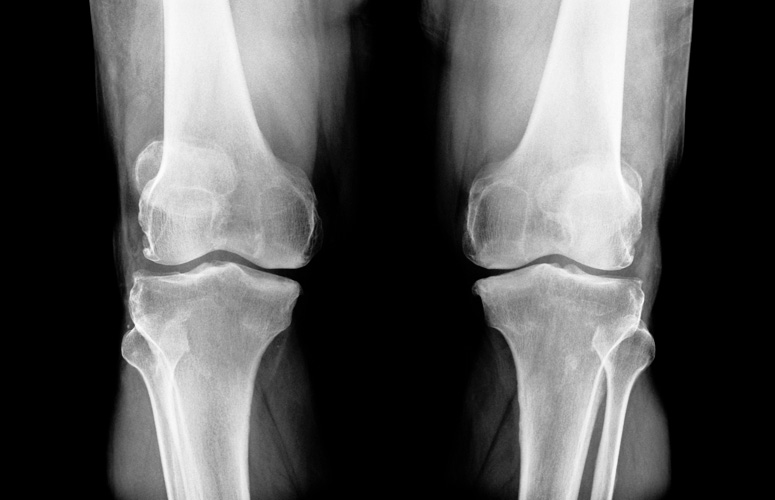

Osteoporosis: qué debemos comer para prevenirla

Vivir con el temor a fracturarse una vértebra, un brazo o la cadera resulta fastidioso. Es lo que les pasa a quienes padecen osteoporosis, que literalmente significa ‘hueso poroso’. La enfermedad se caracteriza por la reducción de la masa ósea y afecta al 30 % de las mujeres mayores de 50 años y al 8 % de los hombres.

La fragilidad ósea que acompaña a la osteoporosis reduce la calidad de vida de las personas que la padecen y se asocia con altas tasas de morbilidad y mortalidad. Además, en numerosas ocasiones se convierte en una enfermedad discapacitante.